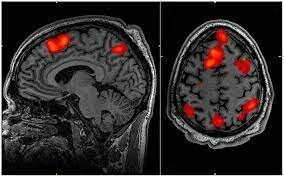

Se fortalece la investigación con el empleo de imágenes no ya anatómicas sino funcionales, en particular la resonancia magnética funcional y la tomografía por emisión de positrones.

Asimismo, surge un nuevo modelo en la interpretación de la organización cerebral de la cognición, el denominado “modelo funcional”. Hasta este momento se había utilizado un “modelo lesional”.